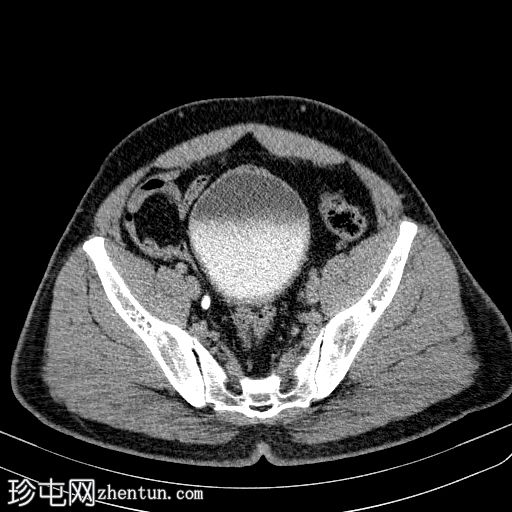

轴位

平扫

在左侧输尿管膀胱连接处可见一枚24×15 mm的大膀胱结石。膀胱壁轻度弥漫性增厚,厚度约6 mm,提示膀胱炎。